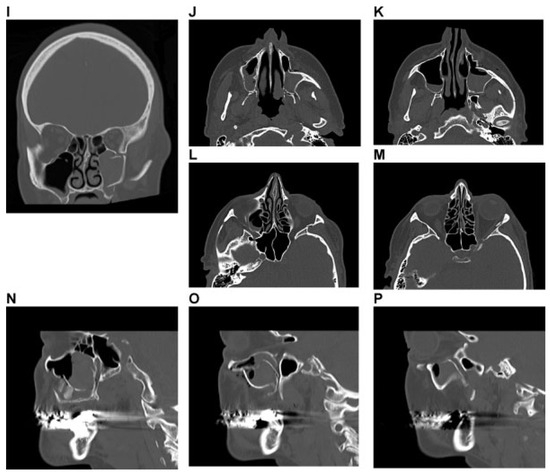

Figure 11.

Panfacial fracture including lower central midface fracture analogous to Hemi Le Fort I fracture. Imaging: Three-dimensional (3D) computed tomographic (CT) scans—(A) frontal view, (B) oblique lateral view right, (C) oblique lateral view left, (D, E) coronal CT scans; (F, G) axial CT scans; (H, I) sagittal CT scans; 3D CT scan details—(J) superofrontal view, (K) palatal from below, (l) pterygomaxillary junction. Narrative description: Midface component of panfacial fracture: LCM fracture left, paramedian midline fracture of the palate; left maxillary alveolar process fracture 11–13, vertical tooth fracture 14, avulsion 15. Details: Dentition (FDI) preinjury: completely dentate. Palate: Paramedian fracture left. Pterygoids: No involvement. Displacement: Anterosuperior displacement of the LCM fragment left, multifragmentation of the antral wall left, Infraorbital rim left intact. Internal orbits: No involvement. (M) Level 3 Code : 91 P.A.S.P - 92 La.P2.L1. This case example CMTR-92-103 is made available electronically for viewing using the AOCOIAC software at www.aocmf.org/classification. Mandible component according to level 2: four fracture regions: condylar process bilaterally, right angle/ramus and symphyseal region. Mandible component according to level 2: four fracture regions: condylar process bilaterally, right angle/ramus and symphyseal region.